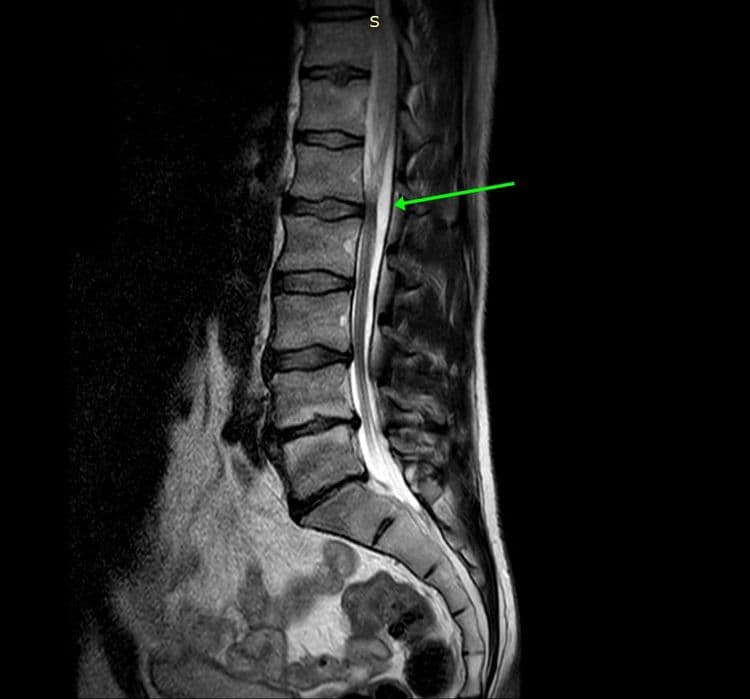

Tumeur bénigne relativement rare de découverte fortuite sur un bilan de lombalgie.

MRI